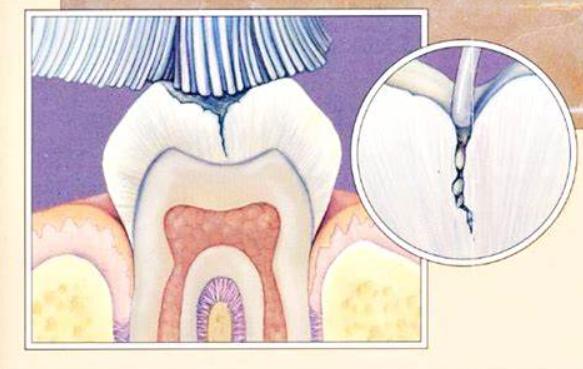

窝沟封闭后的乳牙或恒牙相当于多了一层保护屏障,有效降低食物残渣、细菌等进入窝沟,是预防乳牙龋的主要方法之一(大致过程↓)。

一、先说说为啥小朋友要做新长出来的牙咬合面上的窝沟通常比较深,尤其第一恒磨牙牙面有大小不一的窝沟、点隙,这些地方极易藏污纳垢 。

有时牙刷都刷不到,这些残留在窝沟的食物残渣发酵 ,滋生细菌 ,逐渐损坏牙体,最终导致窝沟龋齿产生。